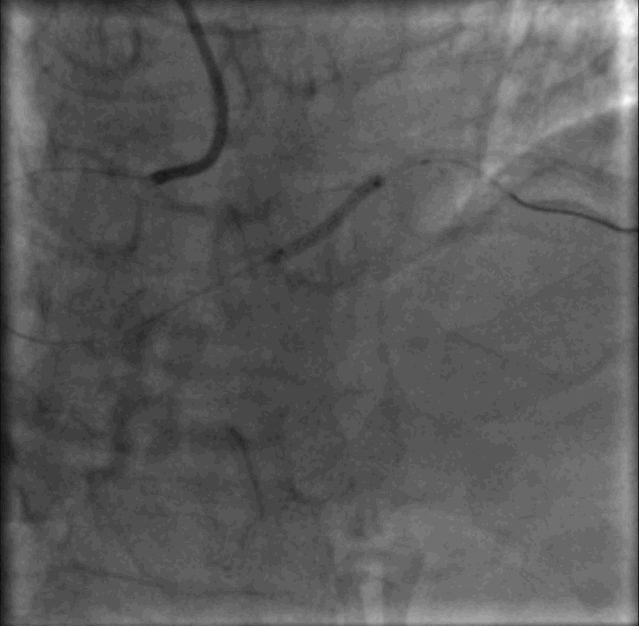

介入治疗——介入无置入

2.5-30mm, 2.75-15mm 两枚药物涂层球囊RESTORE DCB依次扩张RCA-PLA靶病变,贴壁时间45秒~60秒。

介入治疗——DCB介入无置入

继续观察5分钟,复查冠脉造影未见夹层及弹性回缩,患者未诉不适,生命体征平稳。